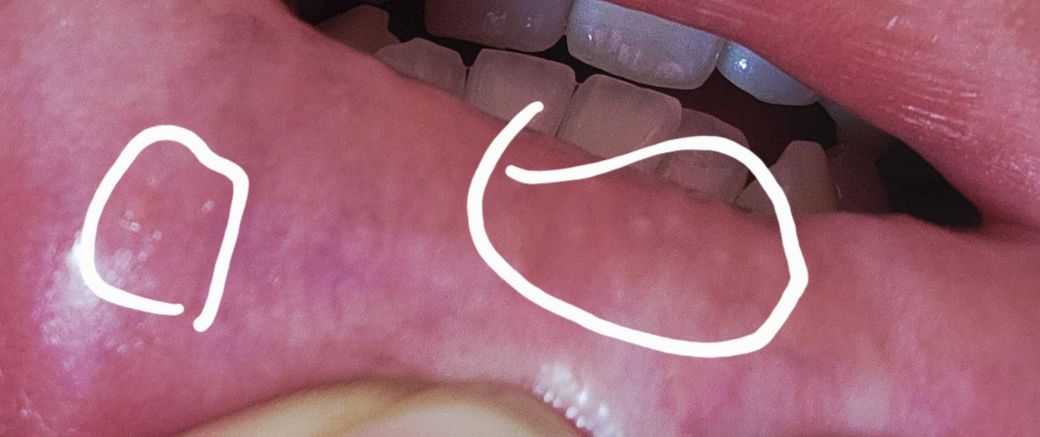

어제 제가 구강성교를 했는데 혓바늘도 뭔가 올라온거 같고 입술 바깎쪽에도 뭔가 이상한게 올라와있고 입술 안쪽 동그라미 친 부위에 뭔가가 올라왔습니다

구강 헤르페스는 보통 입술 바깥이나 입술 경계에 작고 투명한 물집들이 군집으로 생기고, 화끈거림이나 따가움이 선행되는 경우가 많습니다. 반면 입술 안쪽 점막에 단일 병변으로 나타나는 경우는 상대적으로 드뭅니다.

입술 안쪽에 둥글게 하나 올라온 병변은 아프타성 구내염(일반적인 혓바늘) 양상이 더 흔합니다. 이는 스트레스, 수면 부족, 면역 저하, 점막 미세 손상 후에 잘 생기며 성접촉과 직접적인 연관이 없는 경우가 대부분입니다.

다만 구강성교 이후라 심리적으로 불안하실 수는 있고, 초기 헤르페스는 비전형적으로 보일 수 있어 단정은 어렵습니다. 만약 1일에서 2일 내에 투명한 물집이 여러 개로 늘어나거나, 통증과 작열감이 뚜렷해지고, 병변이 터지면서 진물이 나고 딱지가 생기면 헤르페스 가능성을 다시 봐야 합니다.

헤르페스는 수포성 병변을 유발하는데 사진으로 보여주신 모습은 수포성 병변이 전혀 아닙니다.

바이러스에 노출되고 병변이 생기기까지 걸리는 시간이 평균 4–6일 정도 걸리기 때문에 시기로 봐도 헤르페스에 부합하지 않습니다.